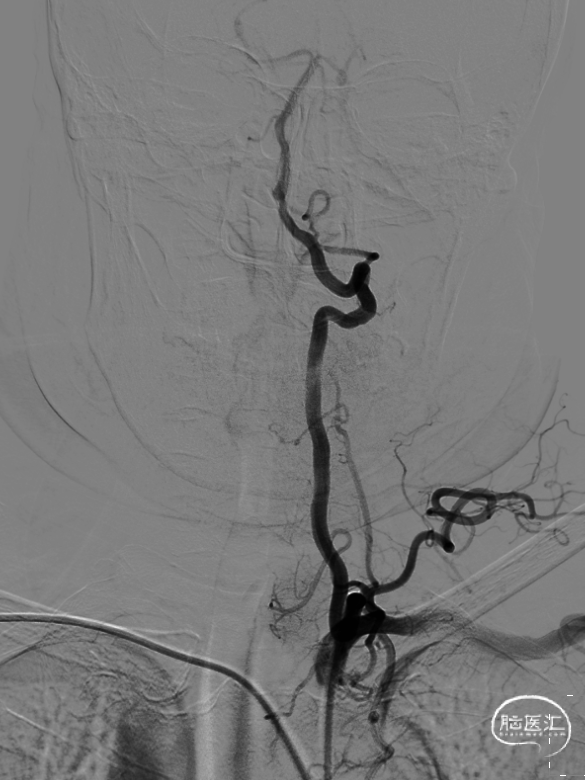

造影结果:

1.右侧桡动脉入路,造影显示:II型主动脉弓,左侧椎动脉V1段走形迂曲,起始部重度狭窄,狭窄率约为75%。

2.患者经桡动脉入路后,减少术后卧床问题,及有效减少穿刺点血肿,假性动脉瘤等并发症。

测量病变:

远端4.27mm、狭窄处0.89mm,狭窄程度约75%。